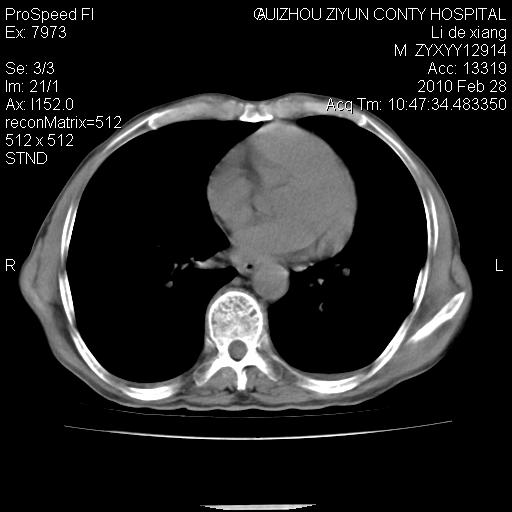

标题: CT24776:男 71Y 咳嗽咳痰胸痛两月,伴声音嘶哑。 [打印本页]

标题: CT24776:男 71Y 咳嗽咳痰胸痛两月,伴声音嘶哑。

左侧中央型肺癌伴左肺上叶阻塞性肺炎及节段性不张可能性大,建议纤支镜检查!

左侧中央型肺癌伴左肺上叶阻塞性肺炎及节段性不张可能性大,建议纤支镜检查!纵隔淋巴结转移.

左侧中央型肺癌伴左肺上叶阻塞性肺炎及纵隔淋巴结转移。

左肺门部肿块,伴左上肺斑块影,周边模糊,支持左肺中央型肺癌伴节段性不张及阻塞性肺炎,结合支气管镜检查。

患者有声音嘶哑,若时间长了,没改变,喉镜检查无异常,可考虑左侧喉返神经受累,因为:左侧喉返神经绕主动脉弓或肺动脉韧带的主动脉端,沿气管与食管之间的沟上行至颈部.

支持肺癌.

左上叶支气管狭窄,阻塞性病变,肺门肿块,纵隔及肺门淋巴结增大,中央性肺癌

左肺中央型肺癌并阻塞性改变、纵膈 淋巴结转移

左侧中央型肺癌伴左肺上叶阻塞性肺炎及纵隔淋巴结转移

支持 左肺中央型肺癌伴左肺上叶阻塞性肺炎,纵隔淋巴结转移。